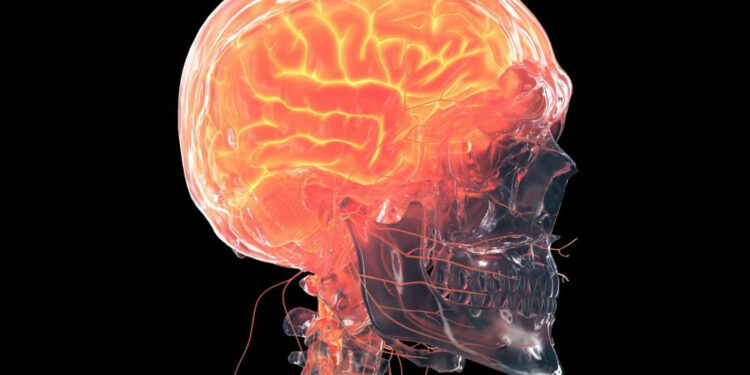

Une étude sur des primates infectés avec le coronavirus a permis de voir en détail quelles zones du cerveau sont les plus touchées et l’ampleur de ces dégâts. Le Covid-19 est une maladie respiratoire, mais qui peut atteindre une grande partie des organes de notre corps, y compris le cerveau. Déjà il y an un, le spécialiste d’imagerie cérébrale à l’hôpital de la Timone à Marseille, Éric Guedj, avait mis en évidence que certains patients développaient une diminution de l’activité neuronale au niveau de certaines régions du cerveau.

Depuis, cette atteinte cérébrale a été confirmée par plusieurs études, montrant qu’environ un tiers des patients avec un Covid-19 développaient des symptômes neurologiques ou psychologiques. Cette atteinte cérébrale multiplierait par cinq les problèmes de mémoire chez les personnes avec un Covid long, augmentant aussi la probabilité de développer une dépression ou des troubles anxieux.

Cependant, le détail des dommages cérébraux était encore méconnu à cause de la difficulté technique à étudier le cerveau des patients humains. C’est pourquoi une équipe de l’Université de Tulane (États-Unis) a décidé d’infecter des primates, afin de pouvoir étudier de près le cerveau d’un individu infecté par le coronavirus. Les résultats, publiés le 1er avril 2022 dans le journal Nature Communications, montrent quelles régions sont les plus affectées et les mécanismes derrière ces atteintes.

Des dégâts cérébraux même après un Covid léger

Un total de huit primates ont été exposés au coronavirus : quatre macaques rhésus (Macaca mulatta) et quatre singes verts d’Afrique (Chlorocebus sabaeus), âgés d’environ 15 ans (ce qui correspond à un peu plus de la moitié de leur espérance de vie en captivité). Ils ont été comparés à quatre primates (deux de chaque espèce) non exposés. Tous les primates exposés ont développé une infection, mais seulement deux ont développé un Covid sévère, obligeant les chercheurs à les euthanasier à 8 et 22 jours de l’infection. Les six autres primates infectés ont développé peu de symptômes respiratoires. Pourtant, les atteintes cérébrales étaient évidentes. “Puisque les sujets n’ont pas eu beaucoup de symptômes respiratoires, personne ne s’attendait à ce qu’ils aient autant de dégâts au cerveau, avoue Tracy Fischer, autrice de l’étude, dans un communiqué. Mais les résultats étaient clairs et nets et il est indéniable que ces dégâts sont dus à l’infection.” Le seul primate infecté qui ne présentait pas des dommages au cerveau était celui ayant été euthanasié à huit jours, ce qui suggère que ces atteintes cérébrales surviendraient dans un second temps après la phase aiguë de l’infection.